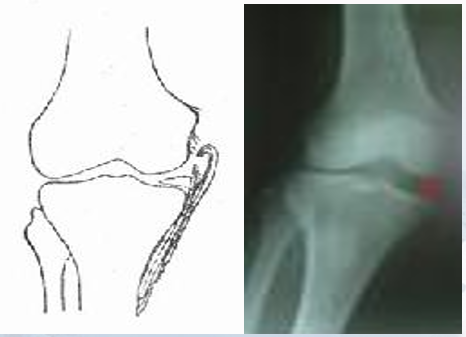

1.带线锚钉治疗侧副韧带止点断裂

膝关节内侧副韧带(medial collateral ligaments,MCL)是膝关节内侧的主要稳定结构,膝关节外侧暴力常常导致其损伤。

传统方法:传统手术治疗膝关节侧副韧带止点撕脱的方法有抽出钢丝缝合法或骨开洞、腱性组织置入固定法等。

由于腱性组织止点区断裂所致远断端残留可供修复的腱组织不足,远断端不能满足缝线的锚定、把持作用,即使勉强缝合,由于缝合后缝线的牵拉力完全负载于远断端腱性组织,导致腱性组织愈合过程中修复区力学强度较弱,难于对抗近端肌肉组织正常牵拉力,易致康复过程中再次发生断裂。

而采用抽出钢丝缝合法,常存在局部皮肤压伤,且钢丝外露,影响外观,不易护理,易致感染,并需再次手术取出。另外,采用钢丝缝合手术操作较为复杂、不仅创伤较大,而且对腱性组织血运破坏较大,极易导致不愈合及抽出钢丝后再断裂发生。

同时,关节固定时问较长,多达6周以上,难以早期进行康复锻炼,术后关节僵硬、局部残留疼痛、原有功能难以完全恢复等,且并发症发生率较高,患者整体满意度较低。

带线锚钉法:将韧带附着骨面小心“鱼鳞状”打毛,并有新鲜渗血。将锚钉拧人韧带附着骨面,用钉尾的编织线编织韧带断端并收紧或用针修补韧带(“8”字缝合或改良Kessler缝合)。